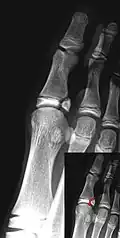

Salter–Harris III fracture of big toe proximal phalanx. -

Salter–Harris IV fracture of big toe proximal phalanx.